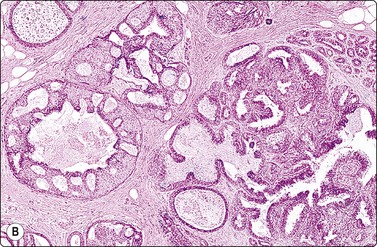

image image

Fig. 7.14 Cystic carcinoma

(A) Obviously malignant epithelial cells with a background of debris in aspirated fluid (MGG, HP); (B) Tissue section showing malignant cells lining the cyst wall (H&E, HP).